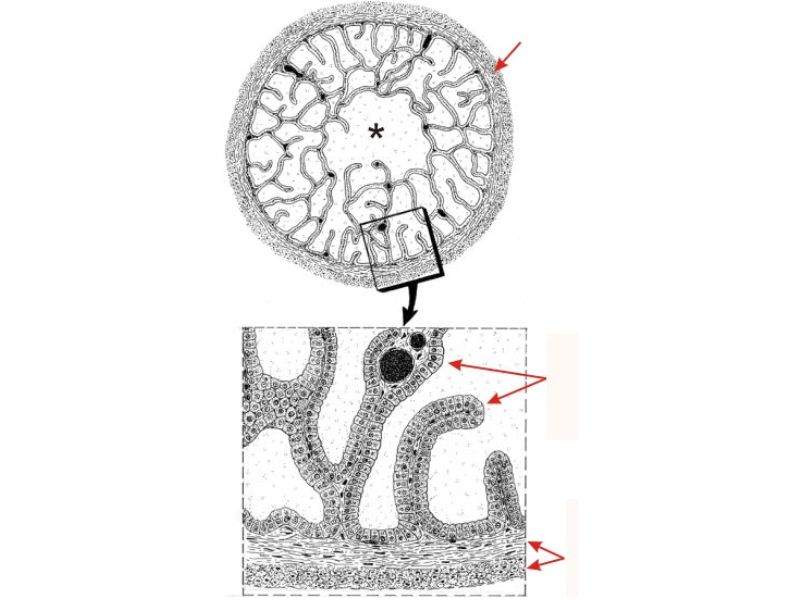

Vesicula seminalis

Slide 81Vesicula seminalis

- Mucosa

- Epithelium

- Lamina propria

- Muscle layer

Mucosa

- Lumen

- Irregular

- Store secretions

- Pseudostratified columnar epithelium

- Lamina propria

- Contains AVL

- Folded mucosa ^^ surface area

Muscle layer

- Inner circular

- Outer longitudinal